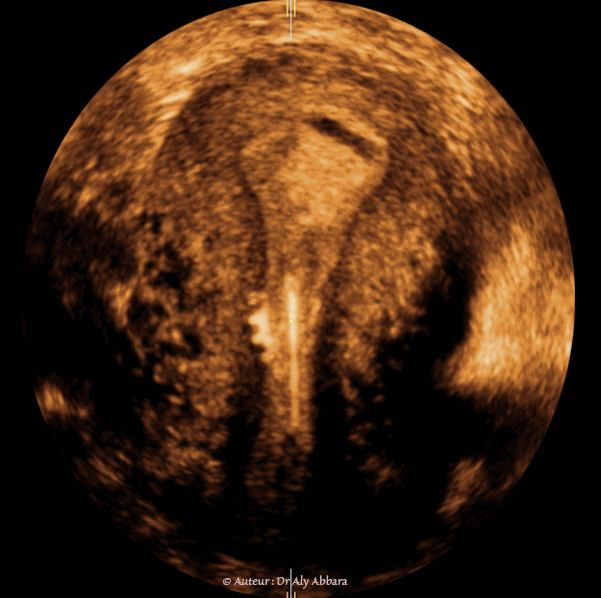

• Images échographiques montrant, sur une coupe sagittale médiane et sur une coupe coronale (frontale), un utérus normal avec le phénomène particulier de rejet de DIU en le déplaçant vers le canal endocervical.

• Ce DIU a été posé trois mois auparavant en remplacement d'un autre DIU qui fut toléré par cet utérus durant deux ans puis il a été expulsé vers le canal cervical sous l'action des contractions utérines.

• Il ne s'agit pas d'un défaut de pose du DIU, parce que le contrôle échographique immédiat après sa mise en place confirme son emplacement correct dans la cavité utérine ; donc de nouveau, pour une raison reste inconnue, l'utérus de cette femme ne tolère plus et rejette ce type de corps étranger après une longue période de tolérance de deux ans (pour le premier DIU).

• Le premier et le deuxième DIU sont exactement du même modèle.

• Le fait que ce DIU possède des crochets latéraux explique pourquoi, une fois que l'utérus l'a expulsé de sa cavité corporéale, il reste souvent accroché aux parois latérales du canal endocervical (comme le montre la 2ème image de cet article).